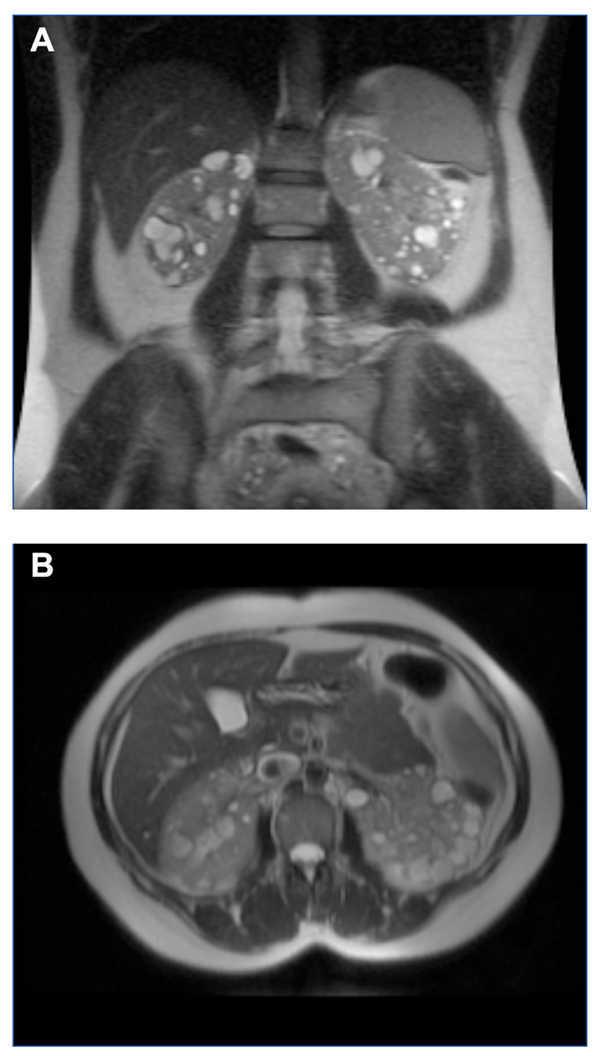

Figure 4. MRI of Case 2 showing enlarged kidneys, with multiple large cysts, a number of which show signs of intracystic haemorrhage (TRV=1322ml). A) Coronal view B) Axial view